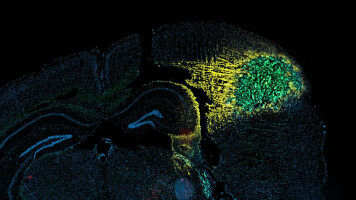

Life Sciences - Health - 19.12.2023

In a study comparing human brain communication networks with those of macaques and mice, researchers found that only the human brains transmitted information via multiple parallel pathways, yielding new insights into mammalian evolution. When describing brain communication networks, EPFL senior postdoctoral researcher Alessandra Griffa likes to use travel metaphors.